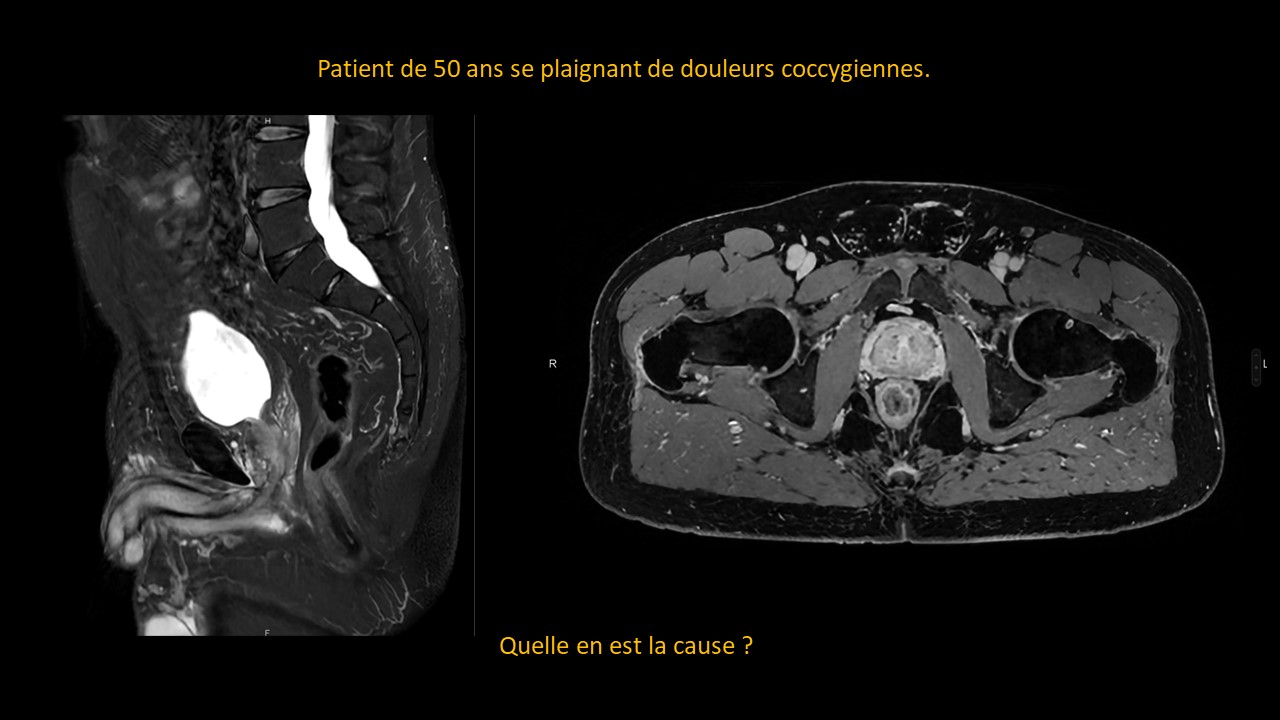

Abdominal